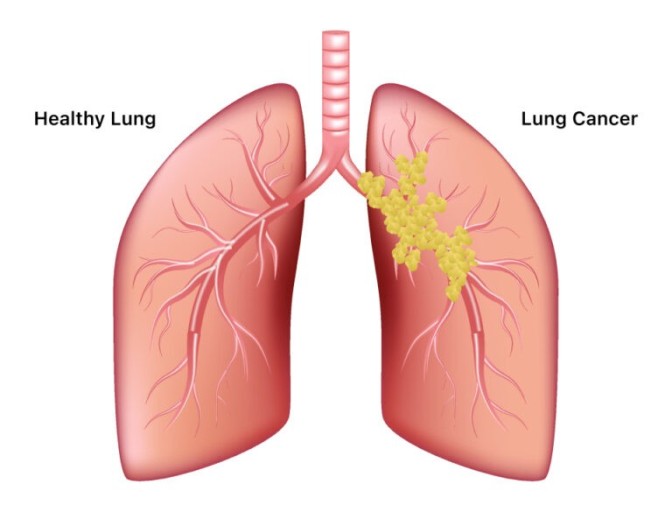

오늘은 단순한 감기와는 달리, 폐에 염증이 생기는 심각한 질환인 폐렴의 증상에 대해 이야기하려 합니다. 폐렴은 세균, 바이러스, 곰팡이 등 다양한 원인에 의해 발생하며, 특히 면역력이 약한 어린이나 노인에게 치명적일 수 있습니다.

폐렴은 보통 갑작스럽게 시작되며, 호흡기 증상과 함께 전신 증상이 복합적으로 나타납니다. 다음은 폐렴 환자들이 흔히 겪는 10가지 주요 증상입니다.